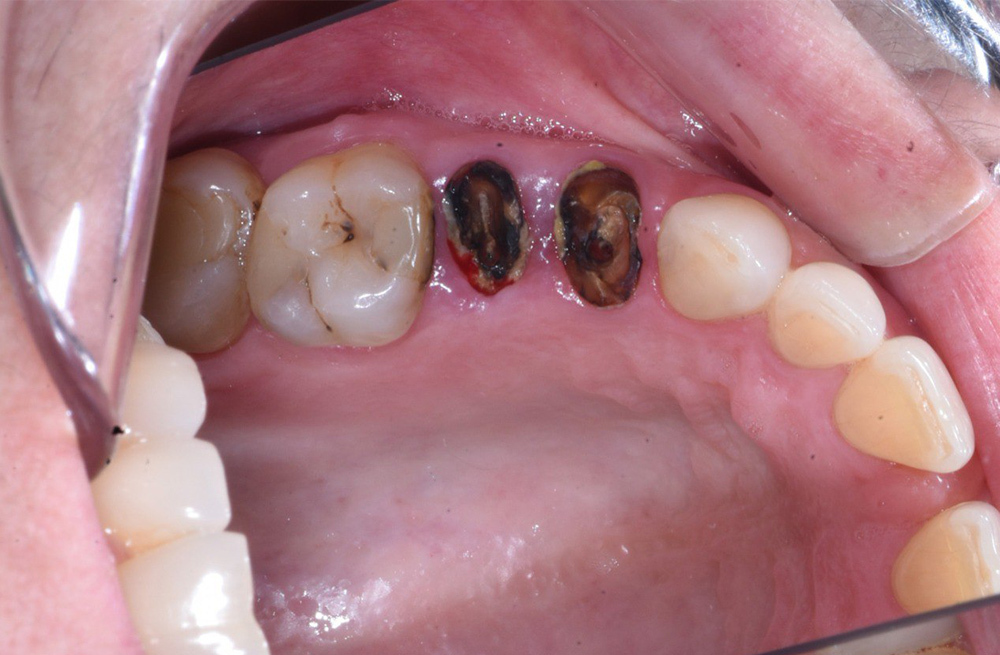

Тотальное восстановление зубов обеих челюстей